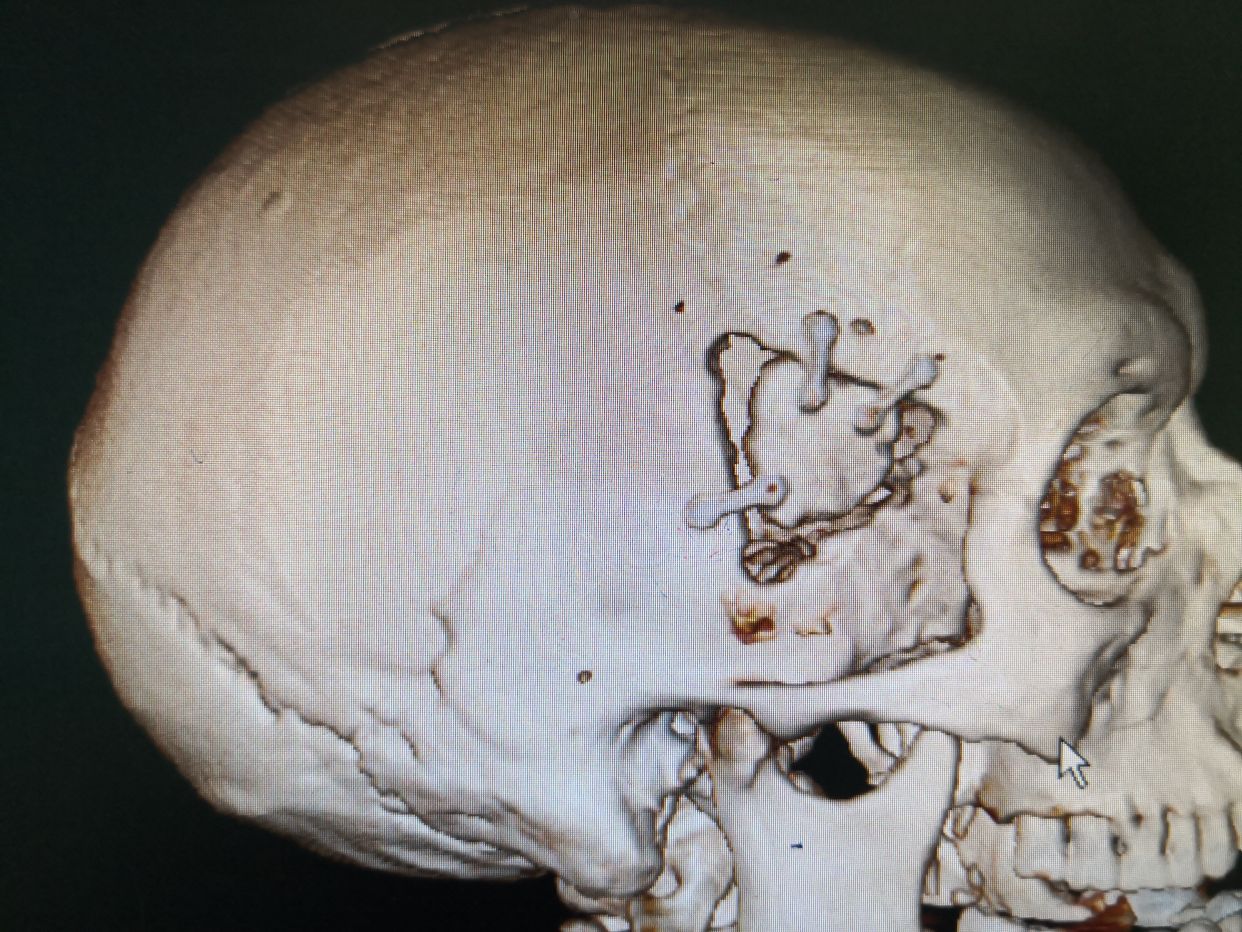

行右侧颞部小骨窗,右侧侧裂岛叶脑内血肿清除术。